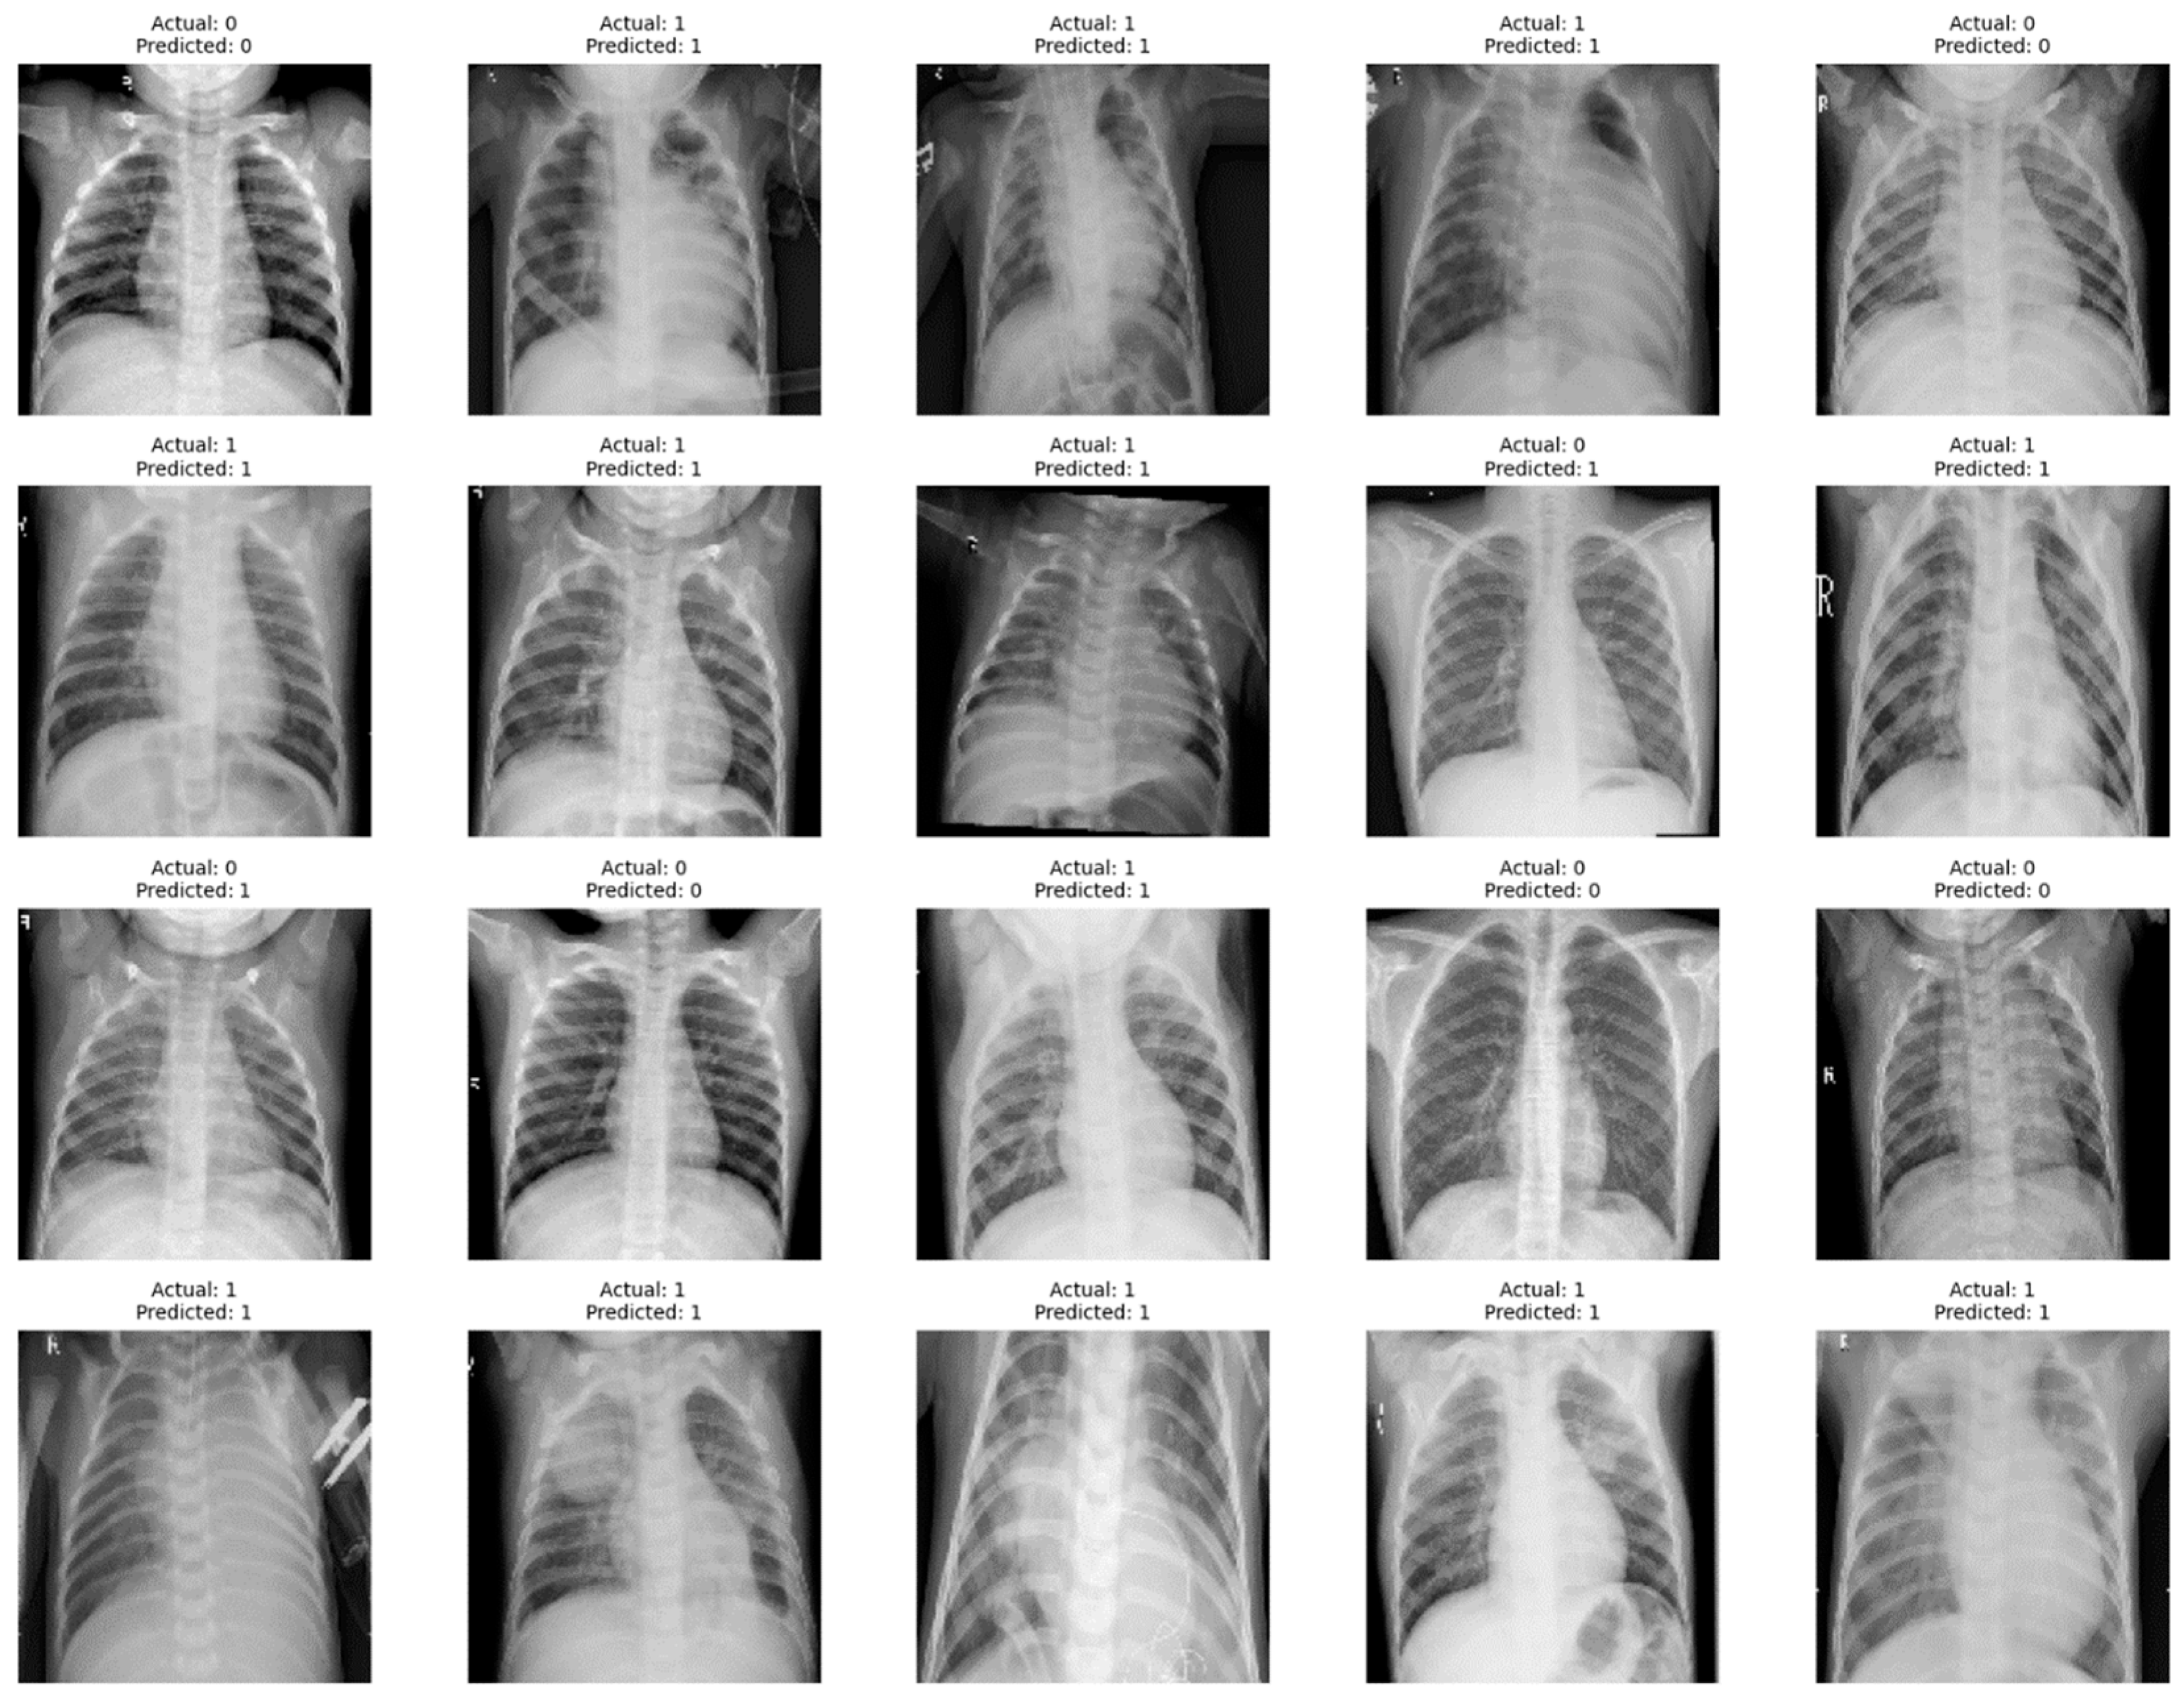

4. Results

- Insight into Class Imbalances: In situations where there is a class imbalance (significant difference in the number of instances between classes), a confusion matrix helps identify how well the model performs for each class.

- Model Comparison: When comparing multiple models, a confusion matrix facilitates a side-by-side evaluation of their performance, enabling stakeholders to make informed decisions about which model is better suited for a particular task.

- Diagnostic Information: The confusion matrix is particularly useful in medical and diagnostic applications, providing information on the model’s ability to correctly identify positive (disease presence) and negative (disease absence) cases.